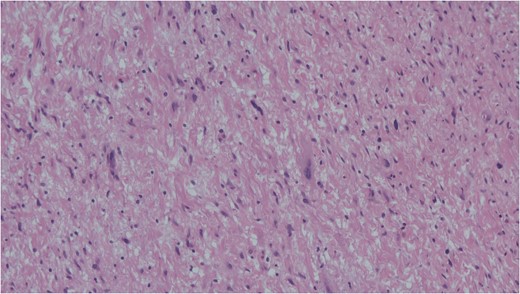

Spindle cells set in a myxoid stroma characteristic of schwannoma. Haemotoxylin and eosin (H&E).

FNAC remains a valuable tool to characterize neck masses but its accuracy in schwannoma is only reported to be 20–25% [4, 6]. Macroscopically, schwannomas are smooth and uniform and often attached to their nerve of origin which may help intra-operative diagnosis. Histologically, schwannomas are encapsulated and consist of alternating Antoni-A and Antoni-B regions [7]. Ancient schwannomas can be recognized by their additional degenerative features such as fibrosis, cystic necrosis and degenerative nuclei [7]. They can often be mistaken for malignant tumours due to nuclear atypia and hyperchromasia [7].